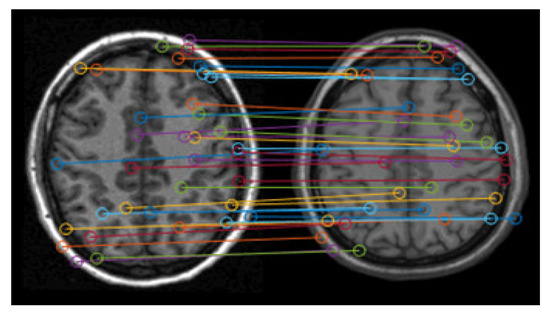

Figure 4 shows the matching results of the feature points. It can be seen that there are lots of error matching pairs of feature points, which may lead to the distortion of registration.

Figure 4. Matching results of feature points.